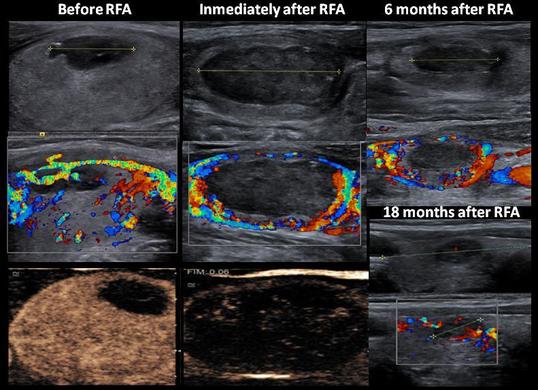

RADYOFREKANSTA TİROİD NODÜL TEDAVİSİ

Tiroid nodüllerinin tedavisinde radyofrekans ablasyon tedavisi günümüzde gittikçe daha fazla kullanılır hale gelmiştir. Belli boyutlara ulaşmış ve kanser bulgusu izlenmeyen nodüllerin tedavisinde uygulanan bu yöntem ile ameliyat olmadan tiroid nodülü tedavi edilir. Lokal anestezi eşliğinde yapılan işlem kısa süre içerisinde biter. Radyofrekans enerjisi verilen nodül yakılarak tedavi edilir. İşlem sonrasında hastanede yatış gerekmez.